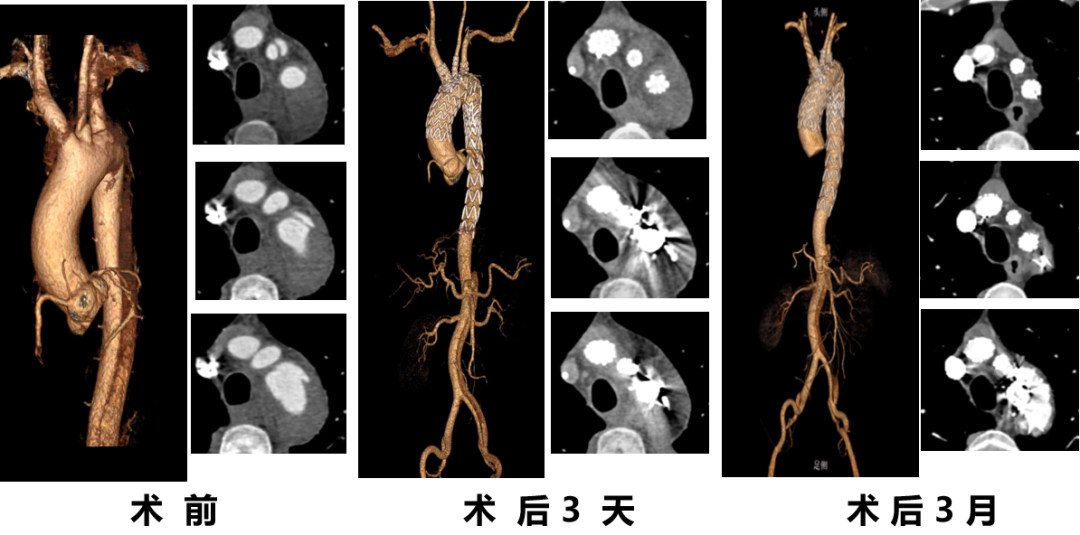

曹某,男,74岁,“胸背部疼痛10天”入院,主动脉CTA提示:主动脉弓可见多发穿透溃疡,较大之一径约1.2cm。高血压病史10年,血压最高190/80mmHg,糖尿病史12年。

术前CTA

术前

术后

手术用时80分钟